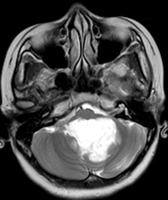

Medulloblastomas

Medulloblastomas are common tumors in childhood, often presenting with vomiting and headache. These tumors are located in midline of the cerebellum (back of the head). Diagnosis is made with MRI, and complete excision can be done safely in majority of the children.